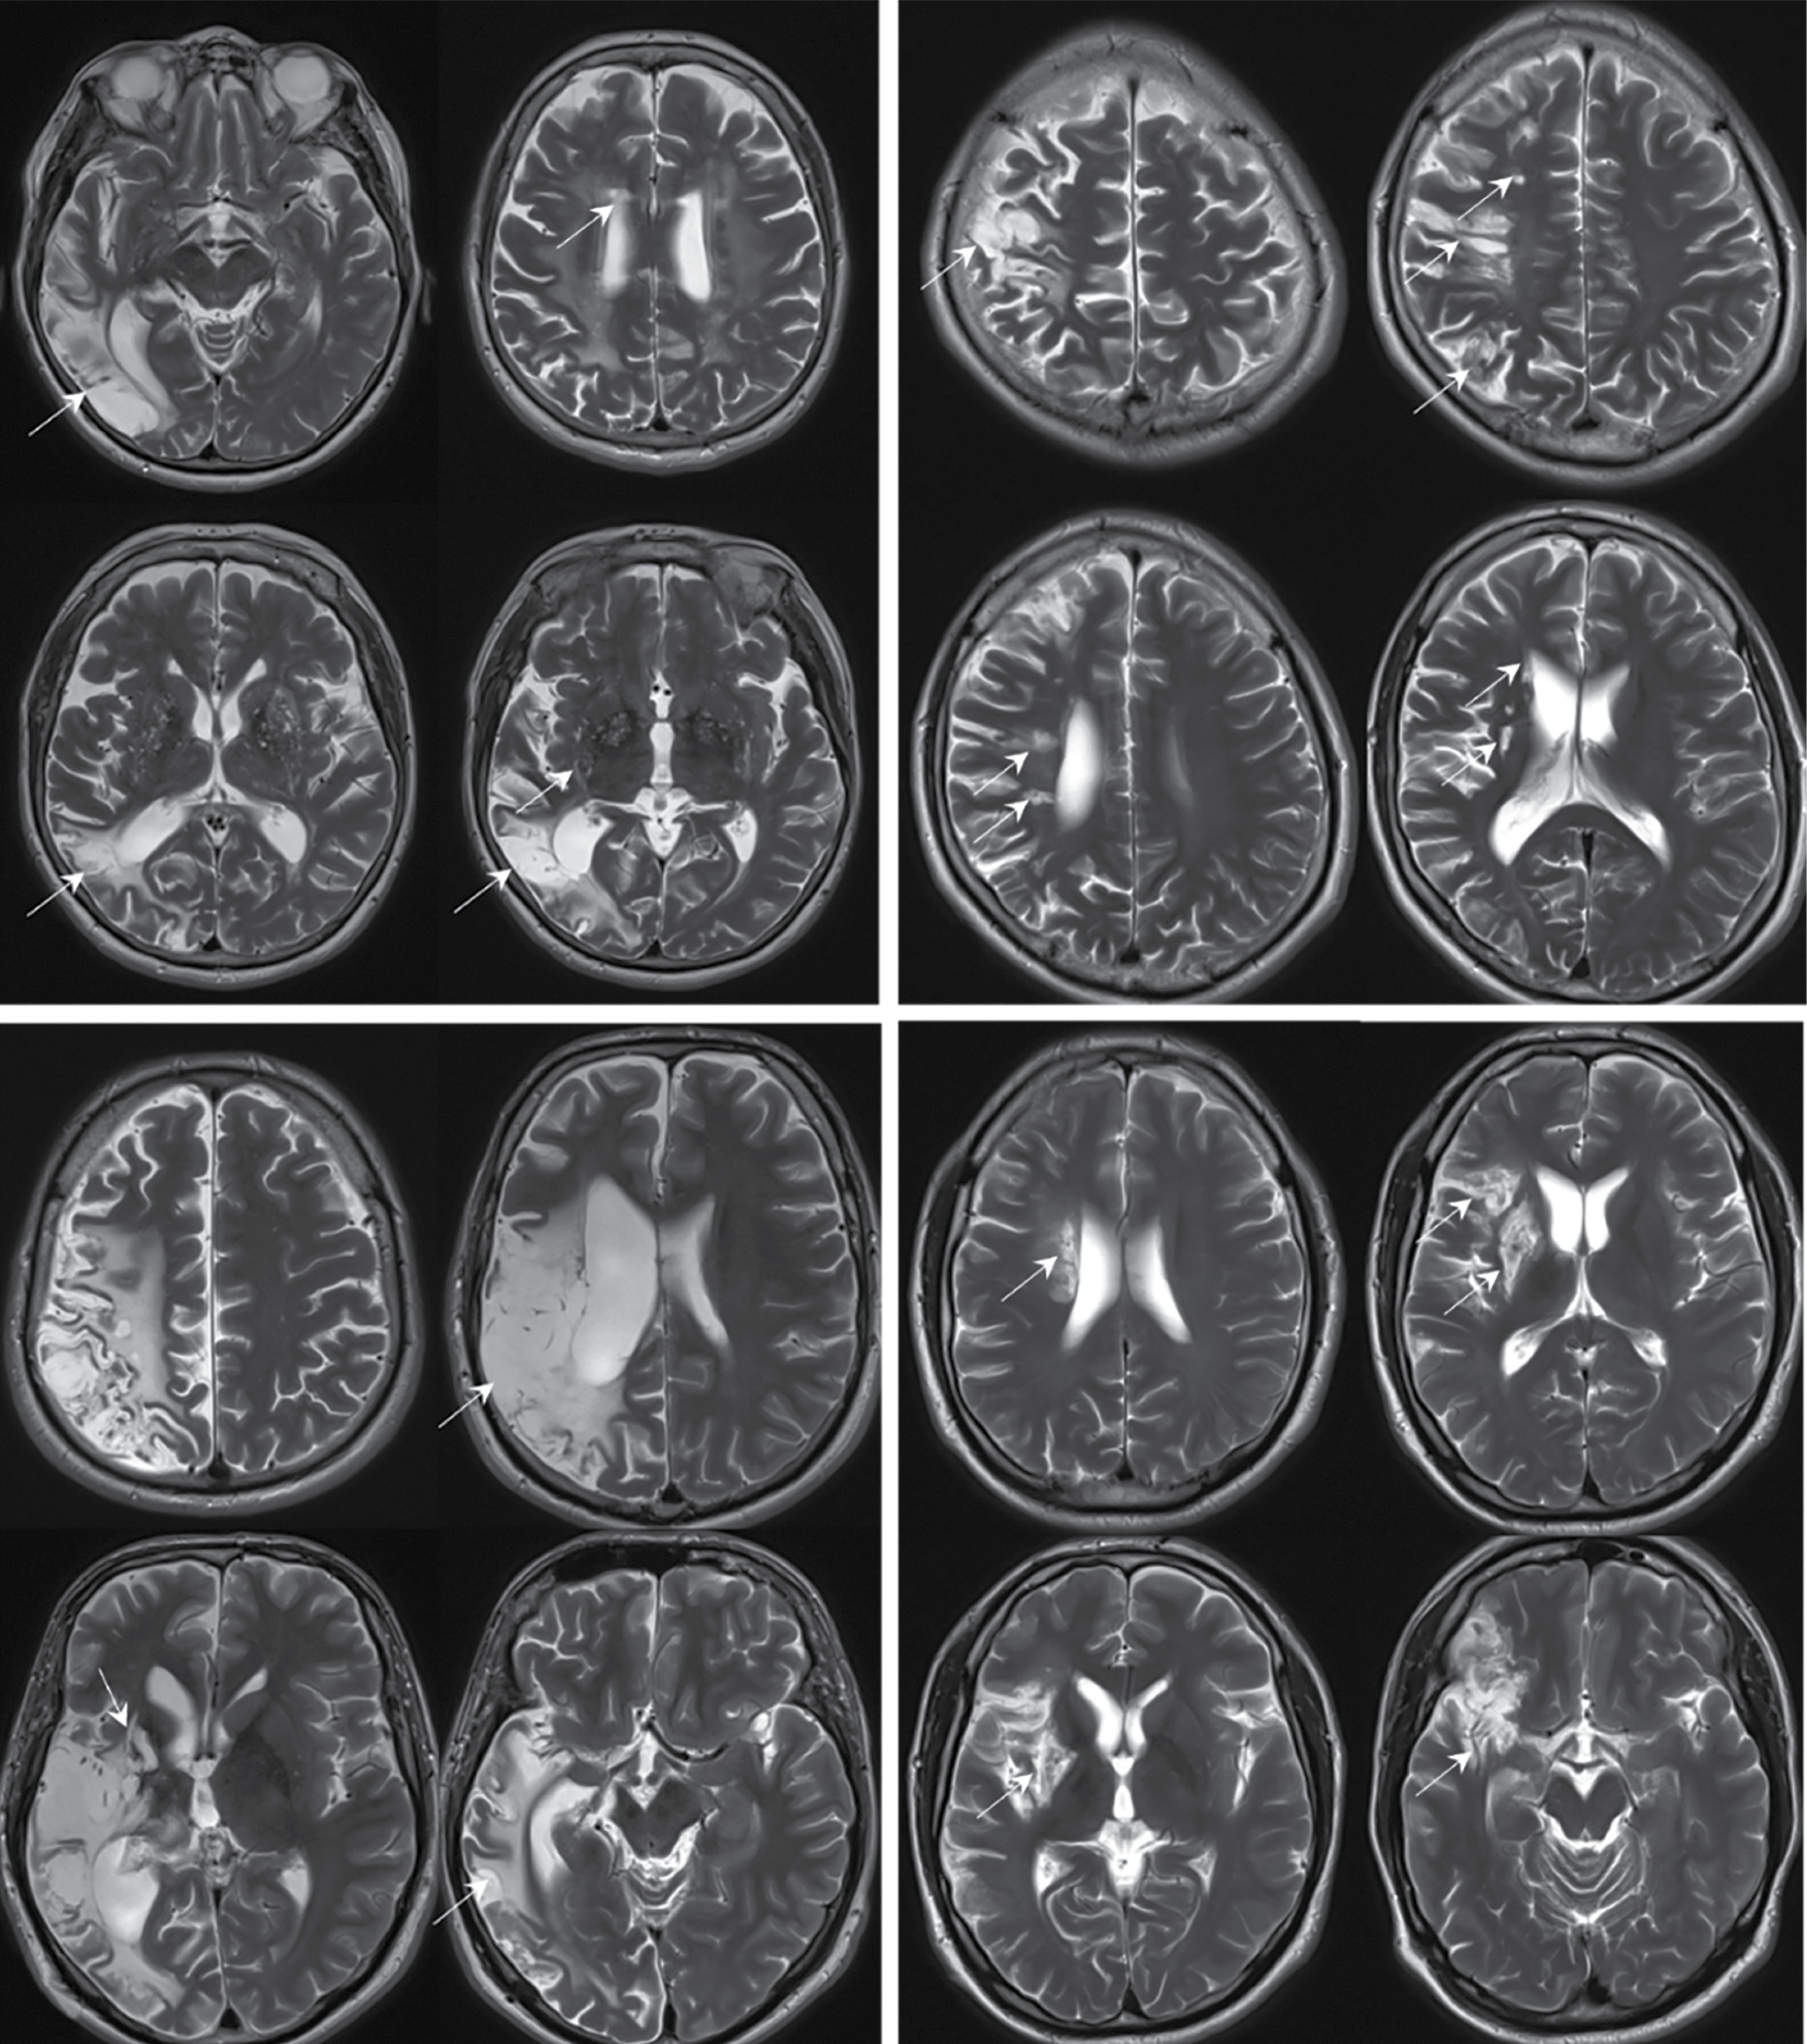

Рис. 3. МРТ головного мозга пациентов с ИП в аксиальной проекции в режимах Т2 (A–D) и ДВИ с b-фактором 1000 с/мм2 (E).

Визуализируются два основных паттерна поражения: небольшие постинфарктные очаги в глубоком белом веществе, базальных ганглиях и стволе мозга (A, B), у 1 пациентки обнаружены очаги острой ишемии в левом полушарии мозжечка (E); крупные корковые постинфарктные изменения в бассейне средней мозговой артерии и зонах смежного кровоснабжения без вовлечения базальных ядер (C, D); постинфарктные изменения (A–D) и очаги острой ишемии (E) указаны стрелками.

Fig. 3. Brain MRI of patients with PV in axial T2 (A—D) and DWI sequences with a b-value of 1,000 s/mm2 (E).

Two main involvement patterns are visualized: small post-infarction lesions in the deep white matter, basal ganglia, and brainstem (A, B); one patient had lesions of acute ischemia in the left cerebellar hemisphere (E); large cortical post-infarction changes in the middle cerebral artery system and adjacent perfusion territories without basal ganglia involvement (C, D); post-infarction changes (A–D) and acute ischemic lesions (E) are indicated by arrows.

Истинная полицитемия

Характерными клинико-нейровизуализационными признаками НМК при ИП являлись инфаркты корковой локализации в зонах смежного кровообращения, стволе, мозжечке, соответствовавшие перенесённым НМК по типу гемореологической микроокклюзии с частотой встречаемости 65%. При ретроспективной оценке клиническая картина была представлена неспецифическими жалобами на головокружение, иногда рвоту, общую слабость, в связи с чем пациенты думали в первую очередь о пищевом отравлении или, в случае отсутствия рвоты, об ухудшении течения основного гематологического заболевания, зачастую не обращаясь за медицинской помощью. В 40% случаев постинфарктные изменения в веществе головного мозга встречались в бассейне вертебрально-базилярной системы, в 60% — в каротидной или зонах смежного кровоснабжения. У 3 пациентов выявлена тромботическая окклюзия магистральных артерий головы с последующим развитием НМК (2 пациента с тромбозом одной из позвоночных артерий, 1 пациент с тромбозом внутренней сонной артерии), при дополнительном исследовании МРТ головного мозга (в режиме Fat Sat) не было получено данных о наличии диссекции сосудов.

Помимо вышеописанных корковых постинфарктных изменений в зонах смежного кровоснабжения, у пациентов с ИП в 35% случаев также встречались обширные полушарные инфаркты с развитием выраженного неврологического дефицита (грубый гемипарез, афазия, гемианопсия) с развитием стойкой утраты дееспособности и инвалидностью (средний возраст пациентов 54 года).

При нейровизуализации основные находки у пациентов с НМК на фоне ИП были представлены в виде двух паттернов (рис. 3):

- небольшие (до 1,5 см) постинфарктные очаги в стволе, мозжечке, глубоком белом веществе и базальных ядрах, корковые постинфарктные зоны, кистозно-глио-зные изменения без вовлечения в процесс базальных ядер, в том числе в зонах смежного кровоснабжения, вероятно, после НМК по типу гемореологической микроокклюзии;

- крупные корковые постинфарктные изменения в бассейне средней мозговой артерии и зонах смежного кровоснабжения без вовлечения базальных ядер.